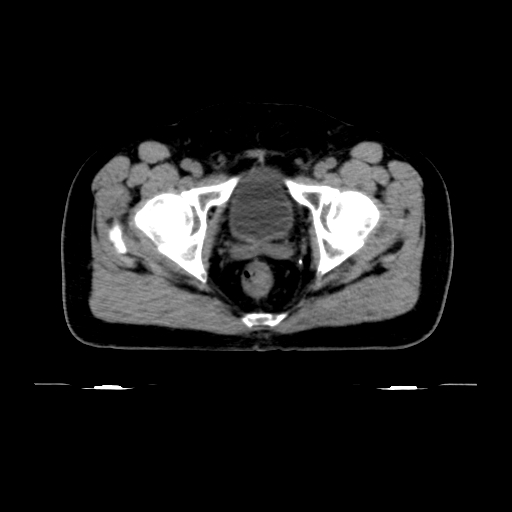

ClearRT® Images

Imaging Information

ClearRT®

Protocol

Pelvis_Normal_medium_50cm

Scan Length

15 cm

KVCT Imaging Time

20 sec